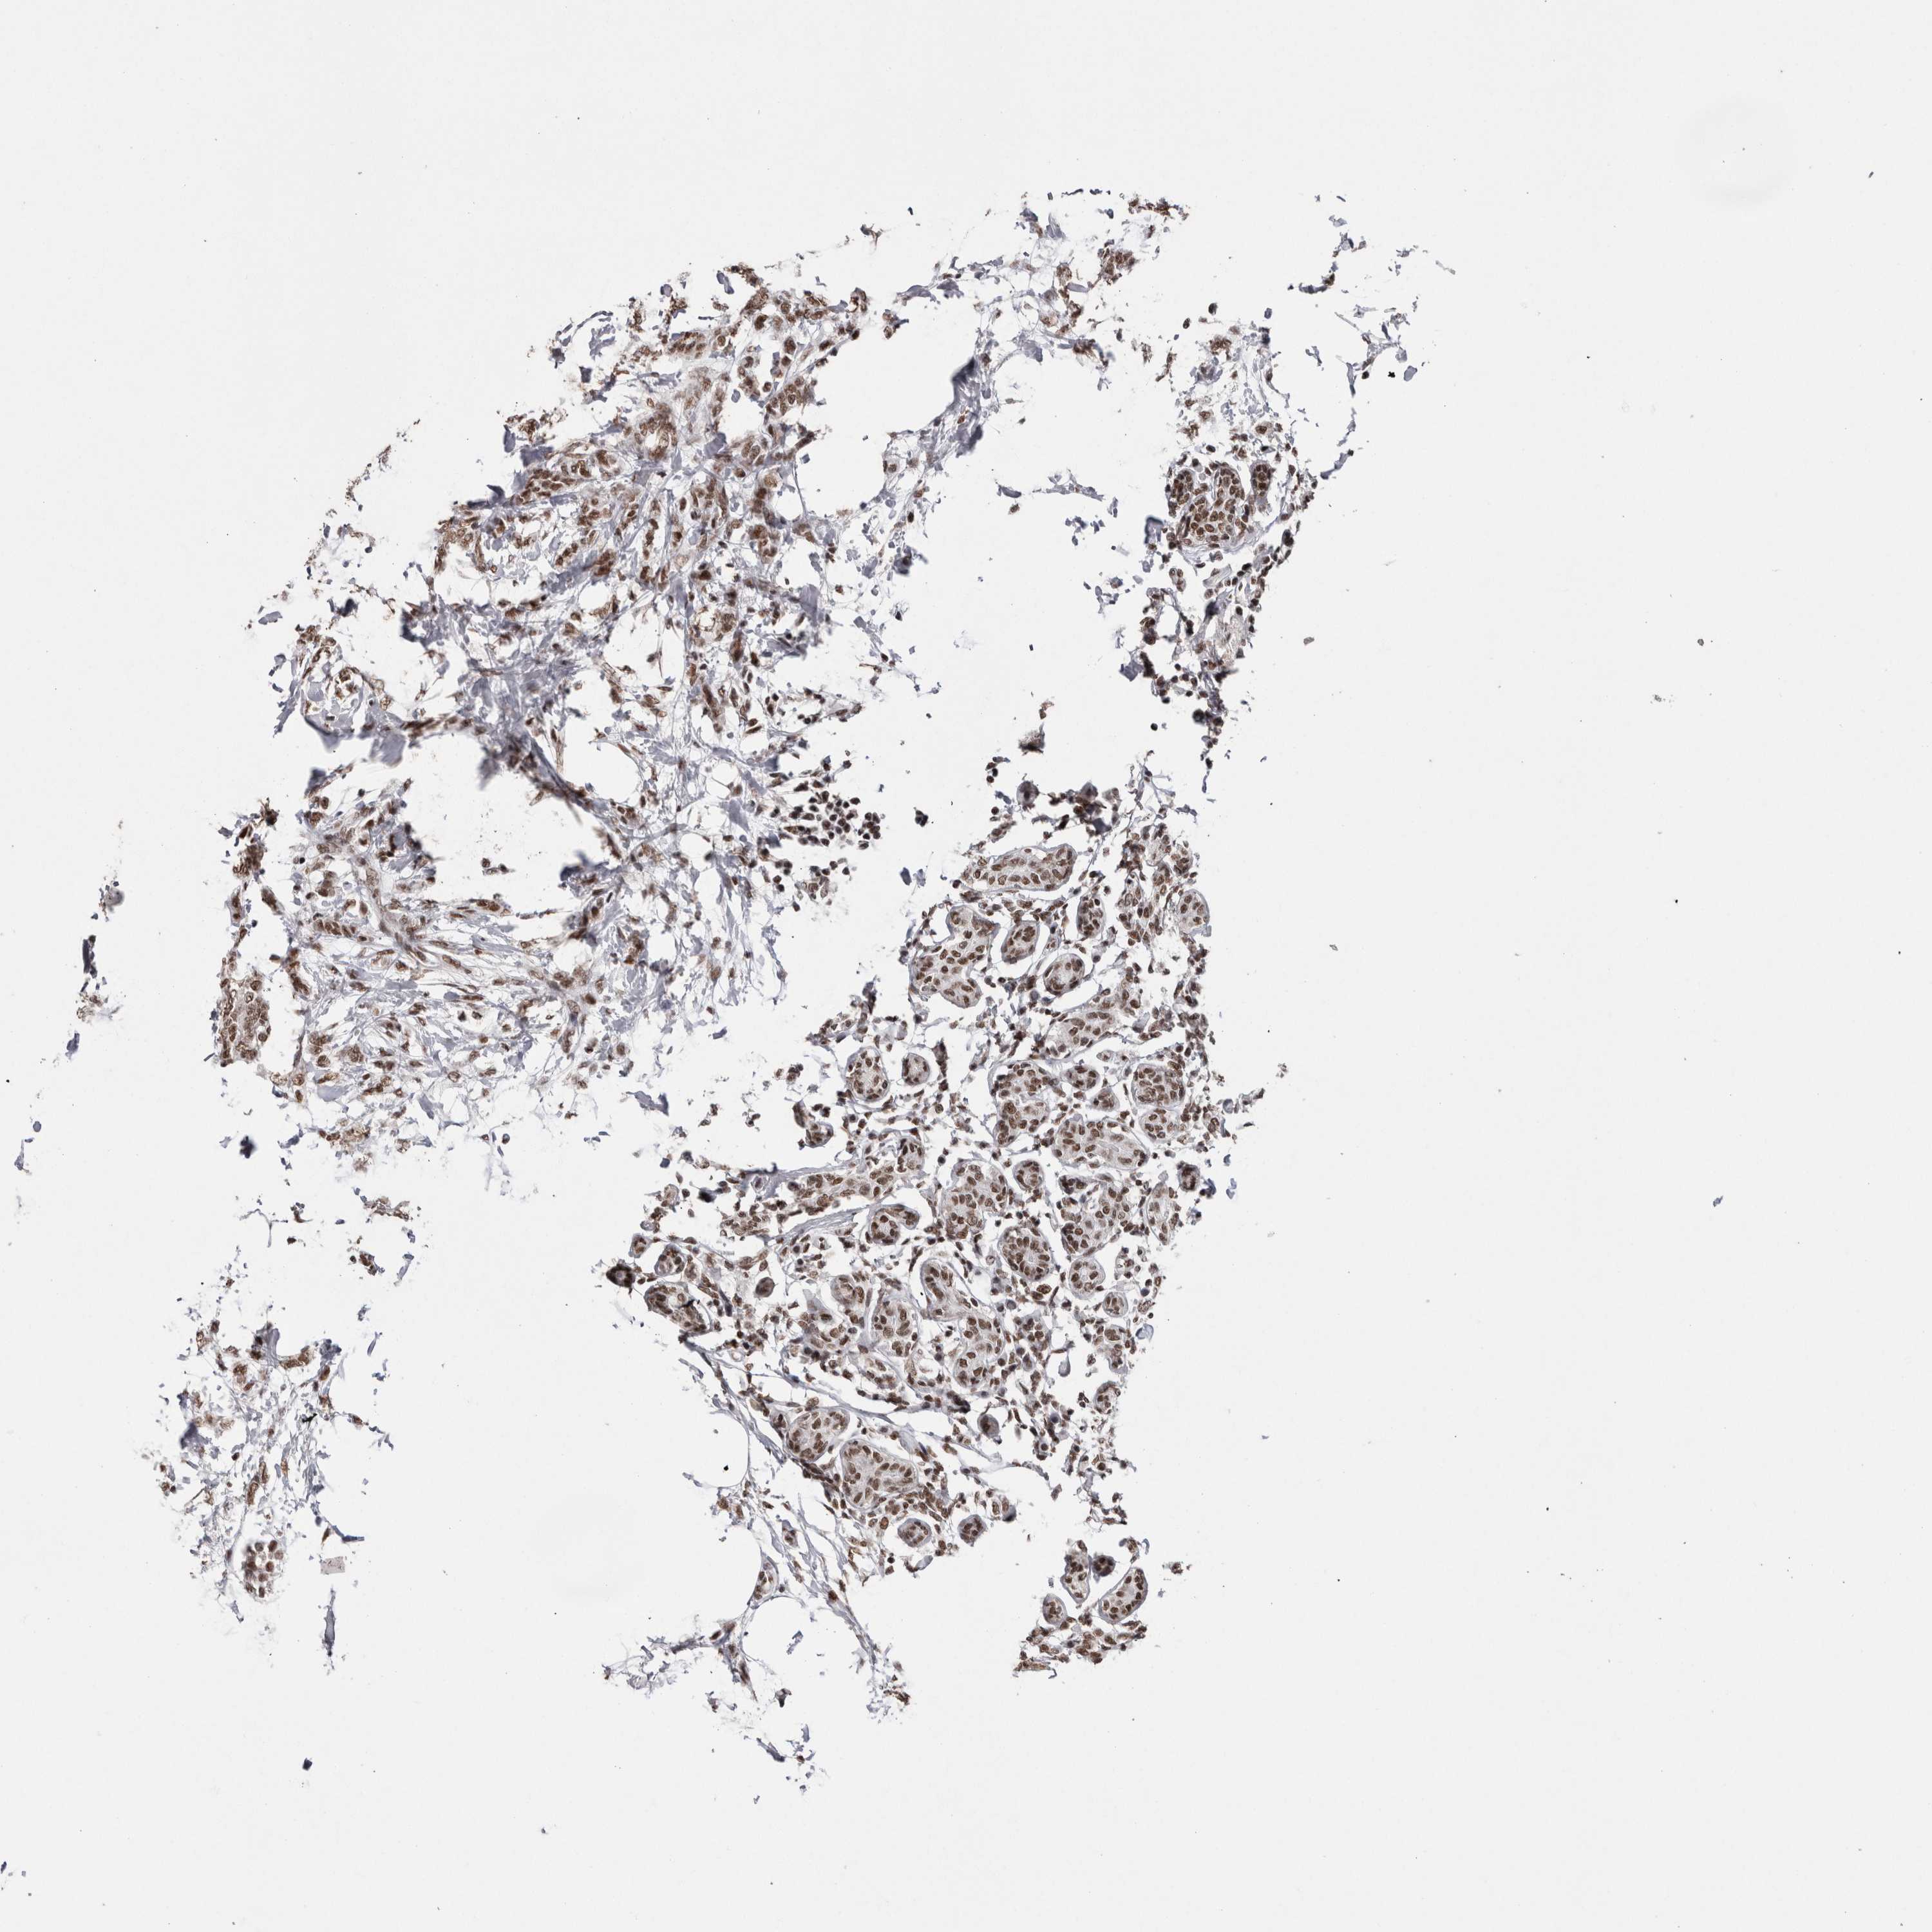

CANCER BREAST CANCER Show tissue menu

BRCA TCGA BRCA VALIDATION PROTEIN EXPRESSION